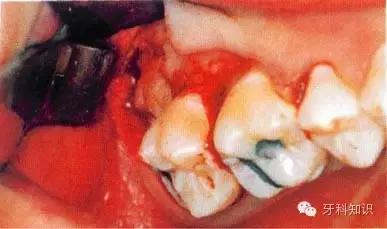

4.断根拔除出:首先要了解每个牙的牙根数目和分布情况。拔除断根时应根据不同情况采取不同方法。如断根边缘露于牙槽骨之间,将牙根挺出。断根位于牙槽窝内或部位很深者,则用骨凿凿除一部分根周骨壁,形成缝隙,然后插入根挺或根尖挺,将断根挺出(图5-12)多根牙折断牙根尚聚在一起者,可用骨凿将联结处劈,分成几个单根,然后分别取出(图5-13、5-14),上述方法仍难拔出的断根,可切开并翻起颊侧粘骨膜瓣,凿除部分颊侧骨质,暴露牙根,然后取出断根,缝合粘骨膜瓣及牙龈。

图5-12 断根拔除法示意图